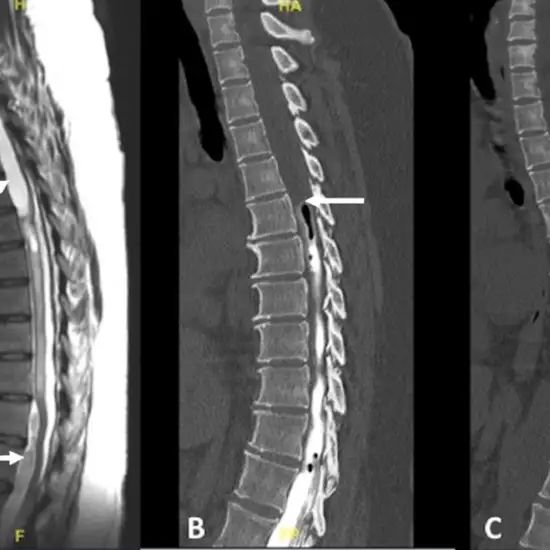

A myelogram is an imaging procedure that looks at the connection between your vertebrae and discs, as well as the spinal cord, nerves, and nerve roots. It determines whether something is actively pressing against your spinal cord, nerves, or nerve roots, causing back pain or numbness and weakness in your arms and/or legs. A radiologist will inject a contrast medium (also known as contrast material or dye) into your spinal canal through your lower back prior to the test. The radiologist may then take a few X-rays of your spine (a computed tomography (CT) scan of your spine after the injection will provide more detailed information.

By injecting contrast into your spinal fluid, a myelogram can show your spinal cord, spinal nerves, nerve roots, and spine bones. As a result, it will reveal anything pressing against your spinal cord or nerves. There are several possibilities for what is causing this pain and creating this unwanted pressure, including: